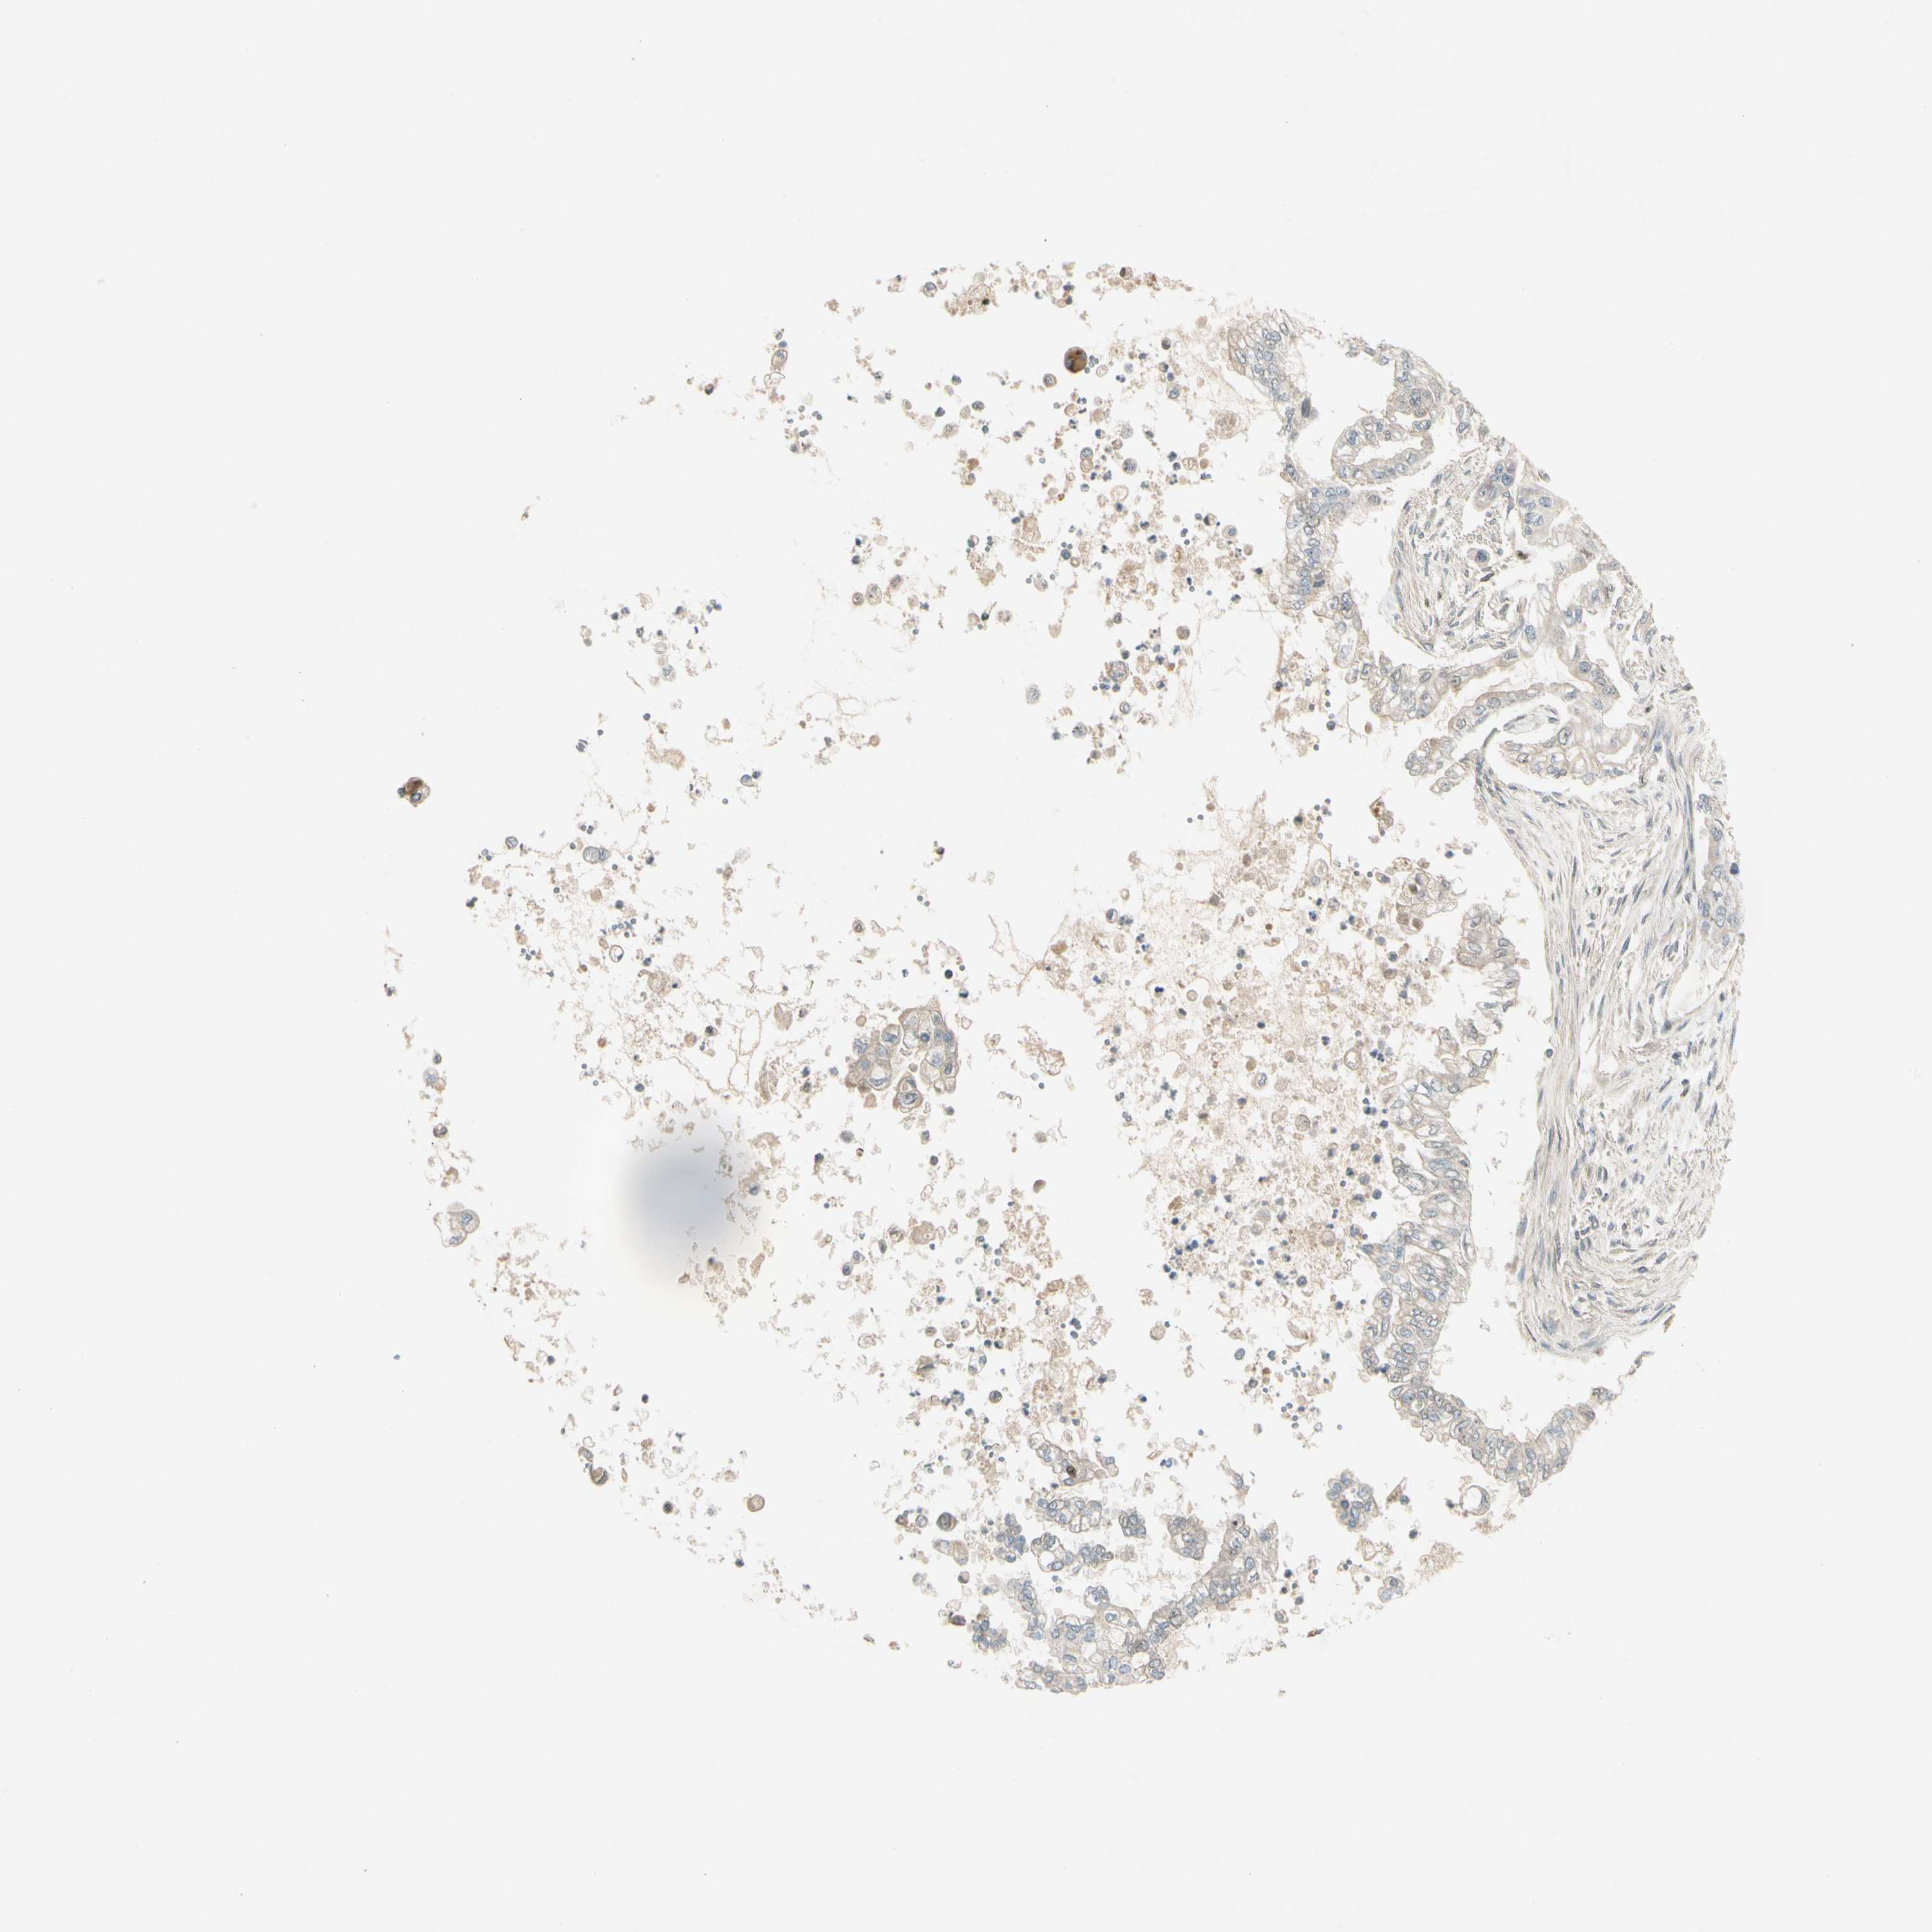

PANCREATIC CANCER - Protein expressioni

A mouse-over function shows sample information and annotation data. Click on an image to view it in a full screen mode. Samples can be filtered based on level of antibody staining by selecting one or several of the following categories: high, medium, low and not detected. The assay and annotation is described here.

Note that samples used for immunohistochemistry by the Human Protein Atlas do not correspond to samples in the TCGA dataset.

Antibody stainingi

Antibody staining in the annotated cell types in the current human tissue is reported as not detected, low, medium, or high, based on conventional immunohistochemistry profiling in selected tissues. This score is based on the combination of the staining intensity and fraction of stained cells.

Each image is clickable and will lead to virtual microscopy that enables deeper exploration of all samples and also displays staining intensity scores, fraction scores and subcellular localization as well as patient and tissue information for each sample.

Antibody HPA007990

Staining

High

Medium

Low

Not detected

Intensity

Strong

Moderate

Weak

Negative

Quantity

>75%

75%-25%

<25%

None

Location

Nuclear

Cytoplasmic/membranous

Cytoplasmic/membranous,nuclear

Adenocarcinoma, NOS